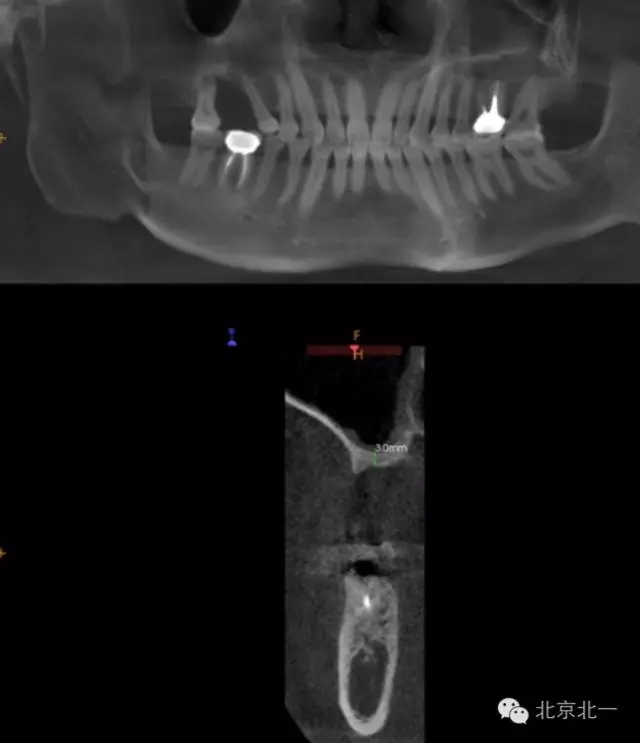

CBCT顯示,骨寬度可,骨高度不足,月3mm。頜間距離增大。

圖二:手術(shù)前全景片

圖三:骨高度3mm.

圖十八:手術(shù)前CBCT

圖十九:手術(shù)后當天CBCT